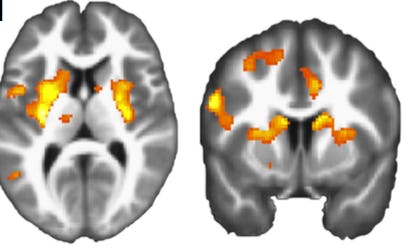

Turns out that people don’t feel too great about paying to hurt others and that this can be seen in the brain. “Most participants displayed moral preferences, placing a higher cost on harming others than themselves,” the researchers write. They found that in the subjects who did decide to shock a stranger in order to earn money, the area of the brain associated with reward and decision-making, the dorsal striatum, was less active than it was when the subjects shocked themselves instead. This regulation seemed to be modulated by the lateral prefrontal cortex, the area of the brain associated with thoughtful action.

In test subjects with stronger moral preferences, the dorsal striatum was less responsive to profit gained from harming others.than profit gained from harming oneself.

Moral systems universally prohibit harming others for personal gain. However, we know little about how such principles guide moral behavior. Using a task that assesses the financial cost participants ascribe to harming others versus themselves, we probed the relationship between moral behavior and neural representations of profit and pain. Most participants displayed moral preferences, placing a higher cost on harming others than themselves. Moral preferences correlated with neural responses to profit, where participants with stronger moral preferences had lower dorsal striatal responses to profit gained from harming others. Lateral prefrontal cortex encoded profit gained from harming others, but not self, and tracked the blameworthiness of harmful choices. Moral decisions also modulated functional connectivity between lateral prefrontal cortex and the profit-sensitive region of dorsal striatum. The findings suggest moral behavior in our task is linked to a neural devaluation of reward realized by a prefrontal modulation of striatal value representations.